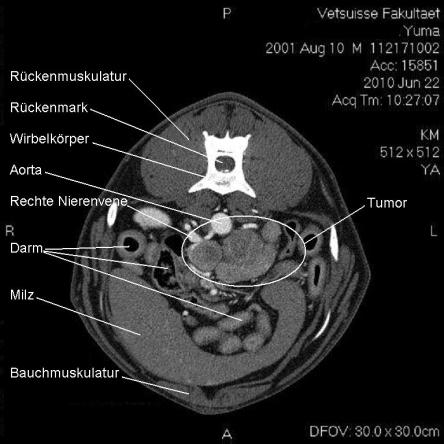

Die Computertomographie (CT) liefert mittels eines röntgenähnlichen Verfahrens ein dreidimensionales Bild des untersuchten Körperteils. Da das untersuchte Tier vollständig ruhig liegen muss, wird Yuma zur Untersuchung narkotisiert.

Im CT wird ersichtlich, dass sich der Tumor, welcher von der linken Nebenniere ausgeht, schon sehr weit in das Gefässystem von Yuma vorgearbeitet hat. Krebsausläufer finden sich wie erwartet in der Hohlvene, aber auch in der Nierenvene sowie in einer weiteren grossen Vene. Der Geschwulst ist somit inoperabel.